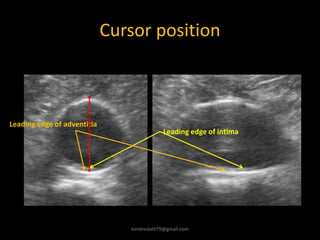

Cursor position

Leading edge of intima

Leading edge of adventitia

Diameter assessment – where to measure

Taken the concept of acoustic

impedance into account the ideal

measurement would be from the

most reproducible measurement

is from leading edge adventitia

ant. wall to leading edge

adventitia posterior wall

The most reproducible

measurement

The true volume flow

From intima to intima